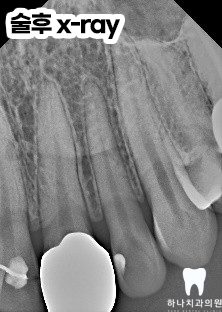

치아 교정 후 설측에 리테이너가

붙어 있는 상태로 위생 관리가 제대로

이루어지지 않아 위쪽 앞니와 옆 치아의

사이에 심한 우식으로 인해

심미성이 많이 떨어진 상태였습니다.

앞니에 발생하는 충치는 겉으로

쉽게 드러나지 않아 단지 작은 점이나

가느다란 선처럼 보이지만

실제로 내부에서는 상당히 진행된

상태일 수 있는데요.

겉에 드러난 변화가 작다고 해서

우식의 범위까지 작다고 단정 짓는 것은

매우 위험합니다.